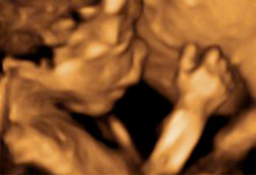

A lo largo del embarazo, el médico te recomendará una serie de pruebas diagnósticas para asegurarse que tu hijo se desarrolla correctamente, como la ecografía. Otras solo se prescriben cuando el ginecólogo sospecha que algo puede ir mal y necesita más datos para corraborarlo, como la amniocentesis o el control del bienestar fetal. Te contamos cómo y cuándo se realizan.